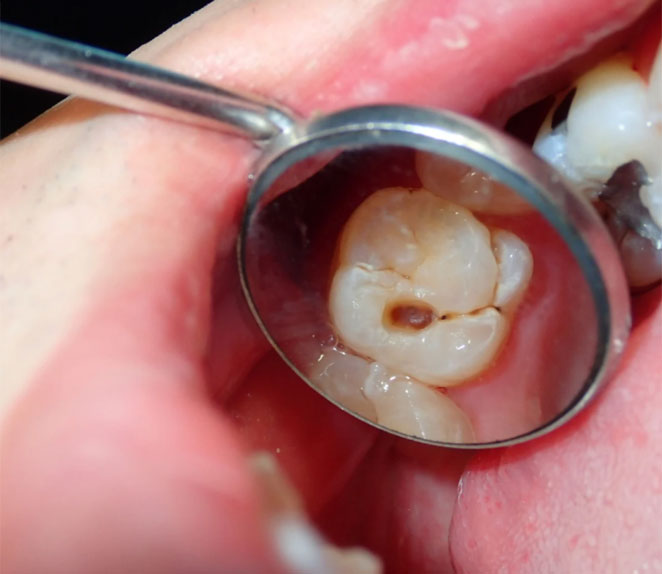

As restaurações dentárias são tratamentos realizados para recuperar a estrutura de um dente que foi danificado, seja por:

- Cáries;

- Fraturas ou desgastes;

- Traumas dentários;

- Troca de restaurações antigas comprometidas.

- Presença de cárie (em qualquer estágio);

- Dente quebrado ou lascado;

Restauração antiga infiltrada ou desgastada; - Pequenas correções estéticas, como fechamento de diastemas (espaços entre os dentes).

Além de evitar dor e desconforto, a restauração ajuda a prevenir complicações mais sérias, como infecções, necessidade de tratamento de canal ou até extrações dentárias.